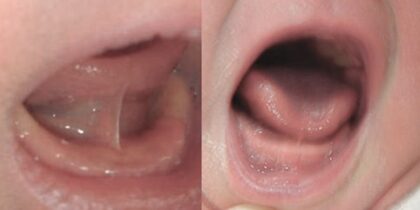

形態異常

(ハート舌)

舌先が歯茎に固定されているため舌先端がハート形に割れたような形態(ハート舌)になります